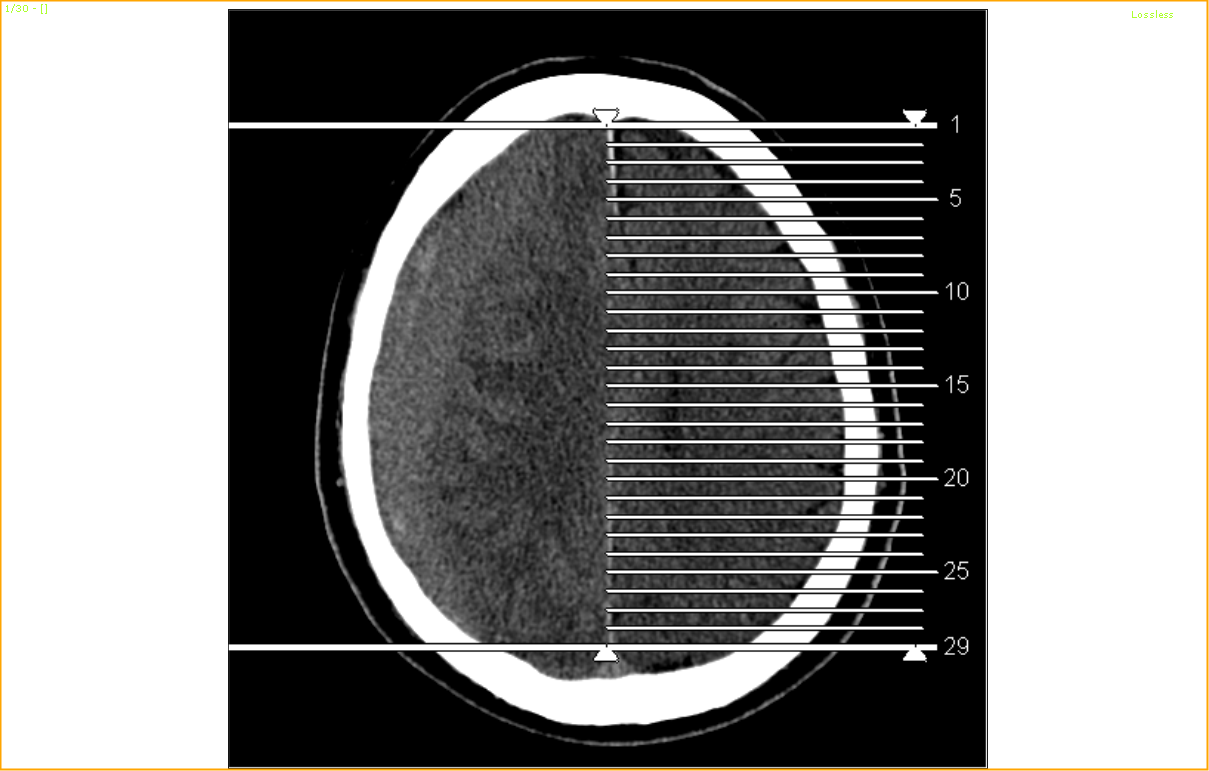

At the same time, came another patient who had a simple fall at home and subsequently noted to have mild left-sided weakness. No loss of consciousness was noted. GCS was full with a power of 4+/5 over the left side and he was admitted as a case of stroke from ER. A CT scan later showed a RT subdural haemorrhage(2.4cm thick) with cerebral edema and slight midline shift of 0.4cm. I had to transfer him to GH neurosurgical unit for evacuation.